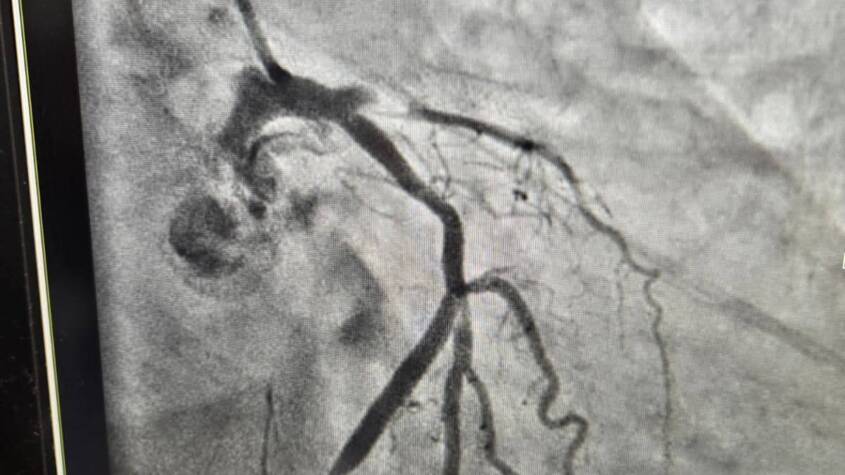

Anantnag, 17 July : The recently established cardiology unit of GMC Anantnag, today, completed 100 primary angioplasties. These 100 cases of angioplasties were performed in a record time period of 3 months and 6 days.

Patients from all around, including Pir Panjal and other far flung areas with acute hearts, were referred to GMC Anantnag for advanced cardiac care including angioplasties for advanced coronary vesicular diseases. The door to balloon time ( a very important parameter for primary angioplasty) has been around 20 to 30 minutes, which is at least 10 minutes less than most of the cardiac centers. All patients had a successful procedure and went home in good health except one mortality. The patient was lost to cardiogenic shock.

The cardiology unit, in addition to primary angioplasty, is performing all high-end coronary procedures, including left main, bifurcation, CTO, and peripheral angioplasty as well.